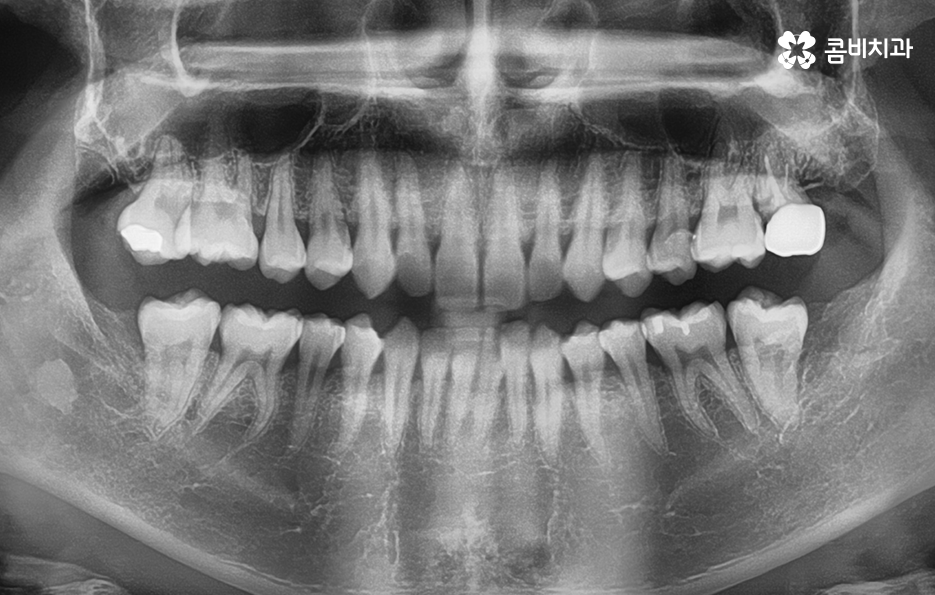

오늘 포스팅에서는 많은 분들이 어금니를 잃게 되는 원인에 대해 살펴보고 어금니 발치후 임플란트 치료 과정이 보통 어떻게 진행되고 있는지 알아볼 거예요 중년이후에 정말 많은 분들이 2차 충치로 인해 치아를 잃게 되는 경우가 많은데 2차 충치란 이미 보철치료를 했던 부위 내부에서 충치가 진행되는 사례로 보철...

오늘 포스팅에서는 많은 분들이 어금니를 잃게 되는 원인에 대해 살펴보고 어금니 발치후 임플란트 치료 과정이 보통 어떻게 진행되고 있는지 알아볼 거예요

중년이후에 정말 많은 분들이 2차 충치로 인해 치아를 잃게 되는 경우가 많은데 2차 충치란 이미 보철치료를 했던 부위 내부에서 충치가 진행되는 사례로 보철 치료 후에 보통 치통이 잦아들고 익숙해지면 별다른 관리를 안하는 경우가 많지만 보철물은 수명이 있고 보철물의 재질에 따라서 보철물이 깨지기도 할 거예요

어금니의 경우에는 금니를 씌웠다고 가정하면 금니 자체가 깨질 우려는 없겠지만 보철물이 오래되면 특히 접착제가 녹아서 치아와 보철물 사이에 틈으로 세균이 침투하여 2차 충치가 발생되는 경우가 많고 나이가 들면서 잇몸이 조금씩 내려 앉으면서 크라운과 치아 사이에 틈이 더 드러나기도 하기 때문에 오래된 보철물은 제때 재치료를 하지 않으면 치아 뿌리쪽으로 충치가 진행되어 발치로 이어지는 경우가 많이 있어요

여전히 많은 분들이 치과에서 크라운 치료를 하면 치료만 잘 받으면 끝이라고 생각하고 별다른 관리를 안해도 된다고 생각하시는 분들도 많지만 크라운 치료는 보통 깊은 충치나 신경치료 후에 크라운을 씌우는 경우가 많기 때문에 신경치료를 한 경우 신경조직이 제거된 상태에서 별다른 통증이나 시림 같은 증상을 못느끼기 때문에 안아파서 별다른 문제가 없다고 착각하기 쉬울 거예요

하지만 위 사진에서 보시는 것처럼 치아에서 통증은 못느끼더라도 2차 충치가 발생되어 뒤늦게 치아 내부의 충치에 대해 알게 되면 이미 치아 뿌리까지 충치가 심각하게 진행되어 크라운 재치료가 어려울 정도로 손상이 진행된 경우도 많으며 결국 어금니 발치후 임플란트 치료로 이어질 수 있어요

신경치료 후 크라운을 씌우게 되었더라도 치아의 뿌리 손상 정도와 치아의 잔존량에 따라서 크라운의 재치료, 즉 재신경치료와 같은 방법으로 자연치아를 보존하는 방법도 있지만 치료 시기를 놓치게 된다면 어금니 발치후 임플란트 시술을 받아야 하기 때문에 오래된 보철물은 주기적으로 검진을 통해 필요하다면 재치료 시기를 놓치지 마시길 바라고 있어요